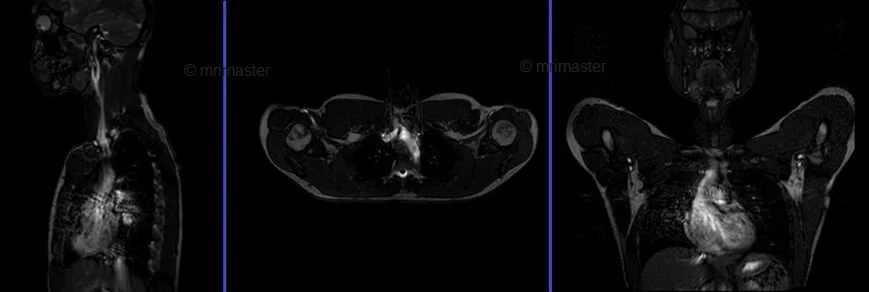

MRA(magnetic resonance angiography) Subclavians care bolus - MRI

Care bolus scans must start one second prior to the contrast administration. The operator can then watch the scans live and wait for the contrast bolus to arrive in the heart. When the contrast reaches the heart, the care bolus must be stopped immediately, and the patient instructed to hold their breath before starting the centric 3D dynamic sequence.

mra abdomen bolus tracking image - MRI